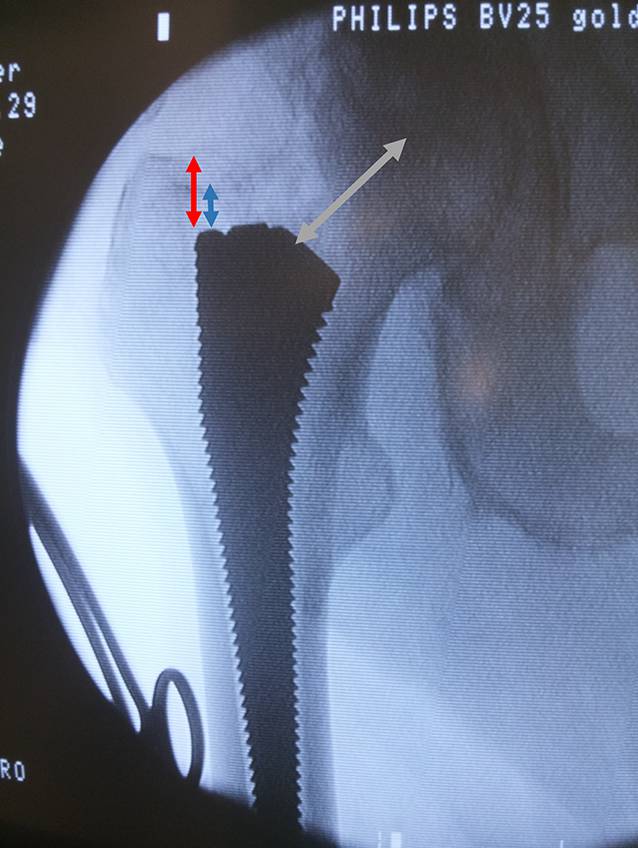

Fig. 9

If desired compare intraoperative radiographic evaluation with the c‑arm and digital planning of the components